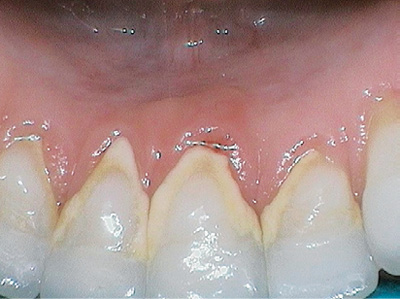

Figure 1: Using a power brush incorrectly.

Figure 2: The same patient six months later using Sonicare with Bluetooth feedback on brushing technique.

Figure 1 shows a patient who was compliant with the use of a power brush daily, but was using it too quickly and in a manner similar to a manual toothbrush. Figure 2 shows the same patient six months later at her next dental hygiene appointment after having switched to a Sonicare FlexCare Platinum Connected. The image reveals a work in progress. While not perfect in her oral hygiene, the difference in the tissue response after having personal feedback during brushing enabled this patient to resolve chronic inflammation at the gingival margin and reduced calculus accumulation substantially. Reduction and prevention of supragingival calculus on the lingual surfaces of lower anterior teeth is so important for patients today to prevent gingival recession tomorrow. However, this is not something the average patient considers. Patients who trust their dental hygienists will be open to their recommendations for using power technology that provides instant feedback to maximize their oral hygiene efforts.